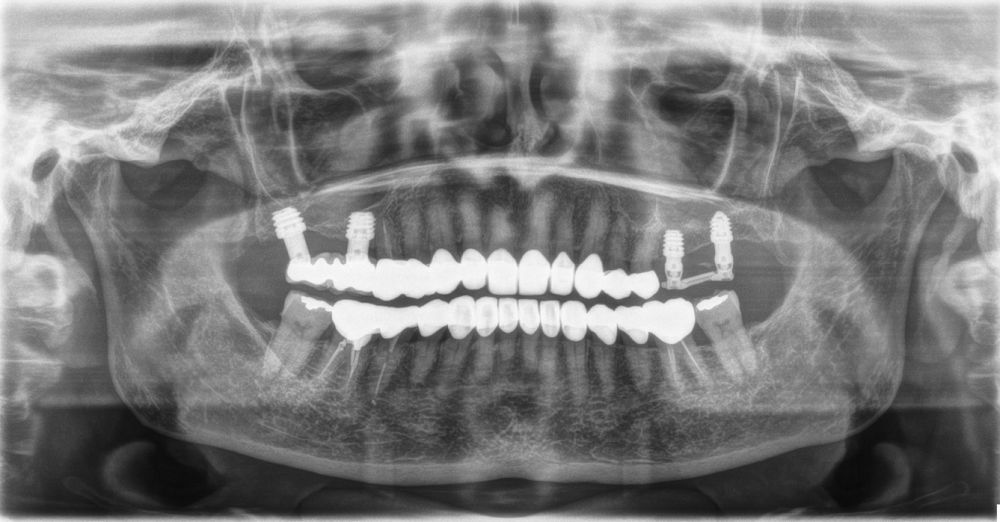

Material y método. Se ha llevado a cabo un estudio retrospectivo de pacientes tratados mediante implantes extracortos (5,5 y 6,5 mm de longitud) colocados mediante elevación transcrestal sin el uso de injerto. Como variables principales se han estudiado: la pérdida ósea crestal de los implantes y la ganancia en altura sobre el ápice. Como variable secundaria se ha estudiado la supervivencia de los implantes.

Resultados. Fueron reclutados 13 pacientes en los que se insertaron 30 implantes. Una vez insertados y cargados los implantes, la altura media final fue de 9,68 mm (+/- 2,66), lo que supone una ganancia promedio de 5 mm. A los 10 años, se observó una disminución media de la altura ósea ganada en los implantes en conjunto de 0, 29 mm (+/- 0,77). La media de la pérdida ósea mesial fue de 0,73 mm (+/- 0,75 mm) y la media de la pérdida ósea distal fue de 0,98 mm (+/- 1,2 mm). La supervivencia fue del 100%.

Material and methods. A retrospective study of patients treated with extra-short implants (5.5 and 6.5 mm in length) placed by transcrestal elevation without the use of a graft was carried out. The main variables studied were: the crestal bone loss of the implants and the gain in height above the apex. Implant survival was studied as a secondary variable.

Results.Thirteen patients were recruited and 30 implants were inserted. Once the implants were inserted and loaded, the mean final height was 9.68 mm (+/- 2.66), which represents an average gain of 5 mm. At 10 years, there was a mean decrease in the overall bone height gain of the implants of 0.29 mm (+/- 0.77). The mean mesial bone loss was 0.73 mm (+/- 0.75 mm) and the mean distal bone loss was 0.98 mm (+/- 1.2 mm). Survival was 100%.